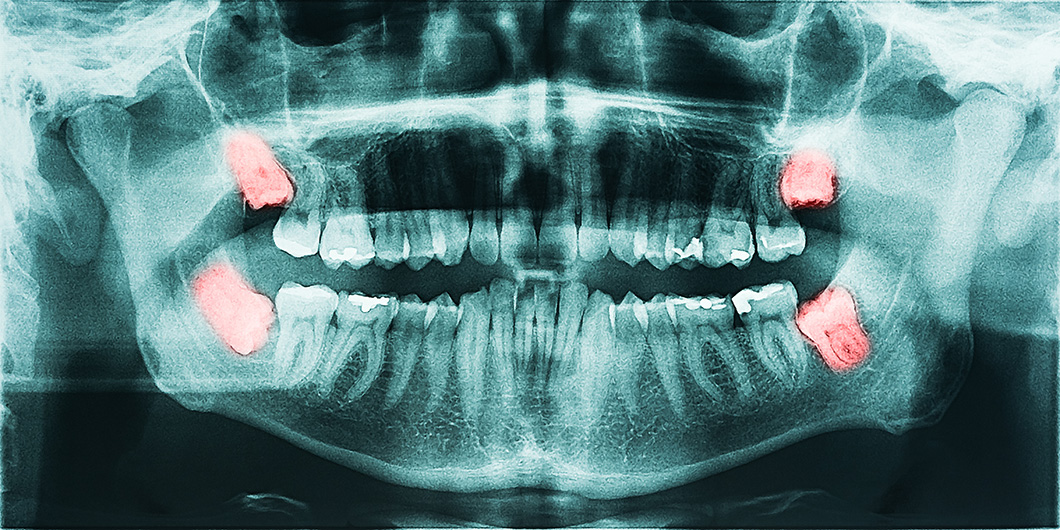

Tooth Extractions in Buena Park

Sometimes it is necessary to extract a tooth. This can happen for a variety of reasons. Extractions are commonly performed in cases where a deciduous “baby” tooth is reluctant to fall out, a severely broken down and non-restorable tooth is present, or “wisdom tooth” is poorly positioned and unable to fully erupt into place.

Pano xray